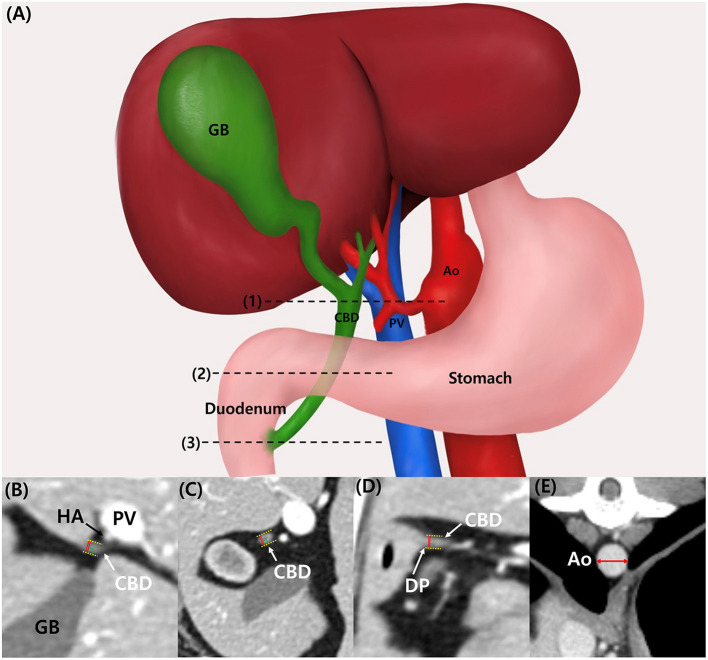

CBD diameter was measured at three different sites: porta hepatis (PH), duodenal papilla (DP) level and mid-portion (Mid) between these points using computed tomography (CT) in 283 dogs without hepatobiliary disease.

CBD diameter was measured at three different sites: at the porta hepatis (PH) level, at the duodenal papilla (DP) level, and mid-portion (Mid) between these points (Figure 1A). At the PH level, the hepatic artery, portal vein, and CBD were located in parallel, and the CBD diameter at the DP level was measured at the location where the CBD inserted into the duodenum. All measurements were performed with only axial plane using electronic caliper. The CBD diameter was measured from the leading edge to the trailing edge, including the ductal wall, and the widest diameter was measured perpendicular to its long axis (Figures 1B–D). CBD:Ao ratio was evaluated at PH, Mid, and DP levels. Ao diameter was measured on the axial plane and at the location where each CBD diameter was measured: PH, Mid, and DP level. For the Ao measurement, minor axis diameter of the vessel was measured (Figure 1E).